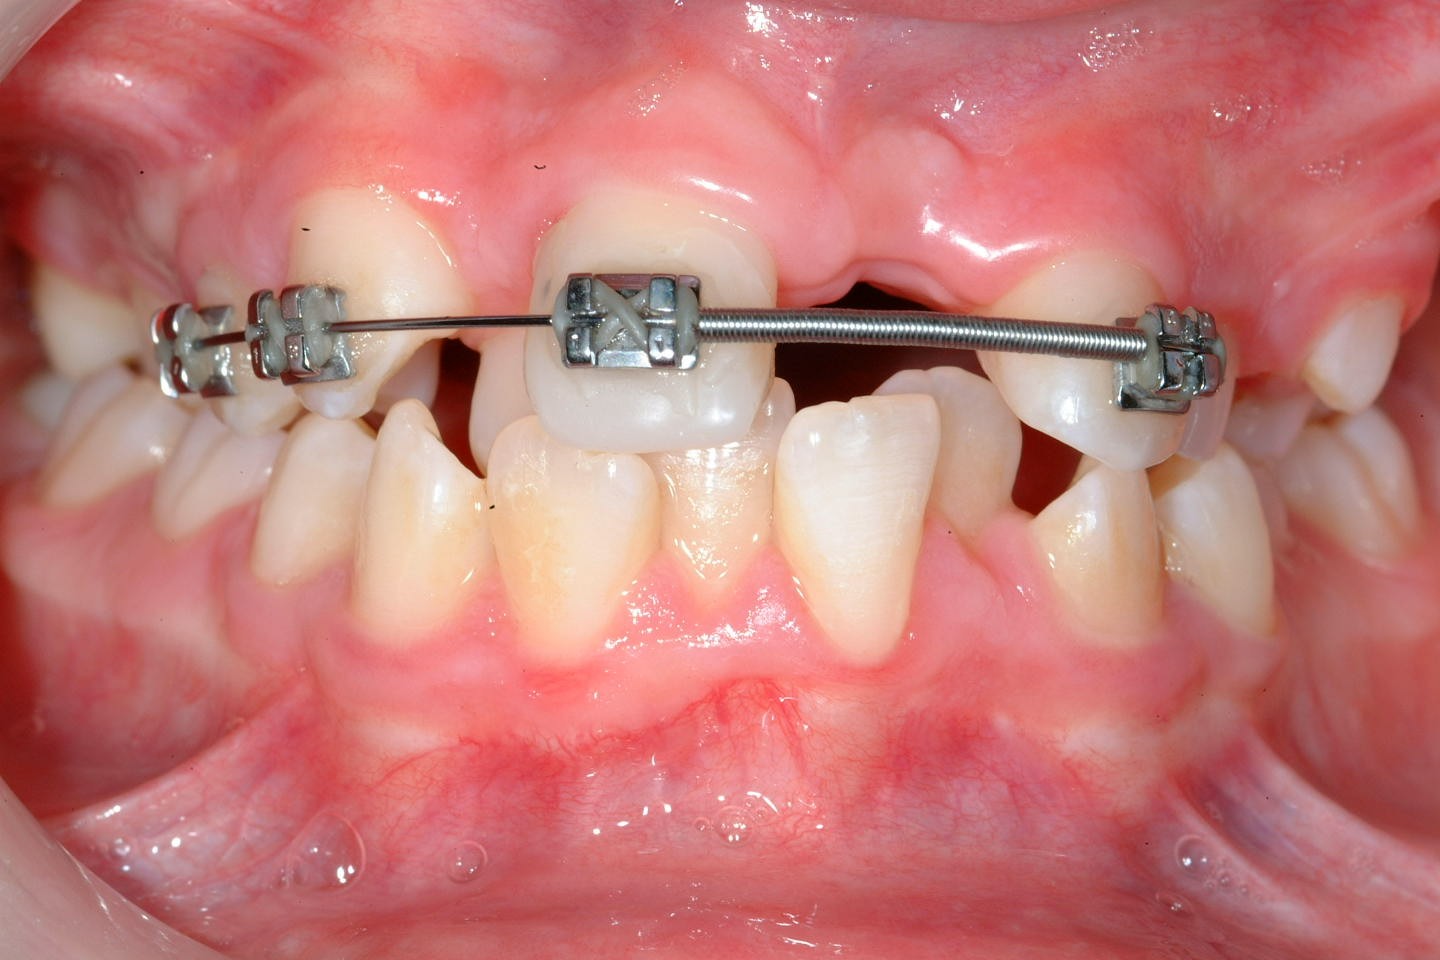

Preoperatively space is created orthodontically (Figure 22). A socket is prepared to accept the tooth using burrs with water irrigation to prevent the bone overheating and subsequent necrosis (Figure 23). If further future eruption would be beneficial (for example in a growing patient) then again, care should be taken to prevent damage to the cementum, otherwise ankylosis may occur which would prevent further eruption.

Once the tooth has been transplanted it should be splinted for between 7 and 14 days. This may be with a preformed splint cemented with a luting material or even with appropriately placed sutures (Figure 24). The area should not be disturbed during the healing phase to allow optimal healing of the periodontal ligament.